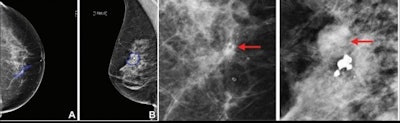

Along with cancer or noncancer classification, the researchers explored whether biopsied lesions detected at mammography could be further classified into more specific subtypes such as DCIS, invasive cancer, high-risk lesions, and benign lesions. The team also investigated whether including clinical characteristics from patients could improve the algorithm's accuracy.

For classifying pathologies, the best-performing algorithms achieved an AUC of 0.76 for DCIS, 0.85 for invasive carcinomas, and 0.82 for benign lesions, respectively. These included both clinical and imaging features in the Israeli training and test sets.

For predicting malignancy in the test sets, the algorithms obtained an AUC of 0.88 for Israeli women and 0.8 for U.S. women (p = 0.006).